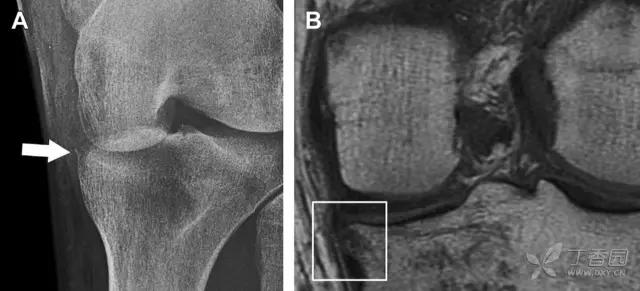

11 Segond 骨折

Segond 骨折是发生在胫骨平台外侧的垂直撕脱性骨折(图 4)。这种骨折在前后位 X 线片上显示最佳。

屈曲位时膝关节受到内旋*力暴**作用,导致皮质骨撕脱性骨折,这种骨折常发生在运动员身上。常引起股骨内髁和胫骨平台后内侧骨挫伤,75%~100% 的患者伴前交叉韧带断裂,33% 的患者伴外侧半月板损伤。

图 4 一位足球运动员的 Segond 骨折

A 正位片示关节线下方胫骨外侧皮质撕脱(箭头)。B MRI 冠状位 T1 加权像示附着于髂胫带的骨折碎片(空箭头)。